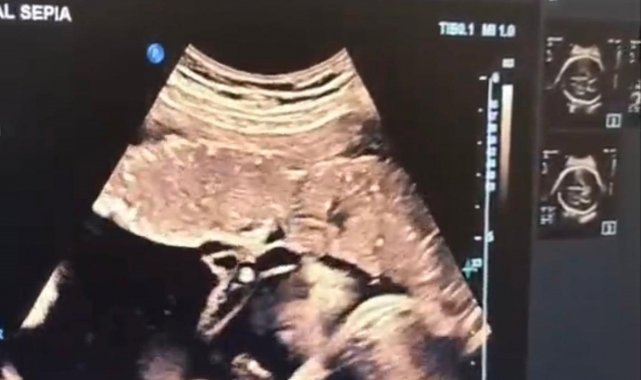

Halk arasında "anne karnında kan nakli" olarak bilinen intrauterin fetal kan transfüzyonu, bebekte ciddi kansızlık (anemi) tespit edilmesi halinde uygulanan hayati bir tedavi yöntemi olarak biliniyor. İşlem, ultrason eşliğinde anne karnından ince bir iğne yardımıyla bebeğin göbek kordonuna girilerek gerçekleştiriliyor. Önce bebeğin kan değerleri ölçülüyor, ardından eksik olan miktar kontrollü şekilde naklediliyor. Lokal anestezi altında ve steril şartlarda yapılan müdahale yaklaşık 30-45 dakika sürüyor.